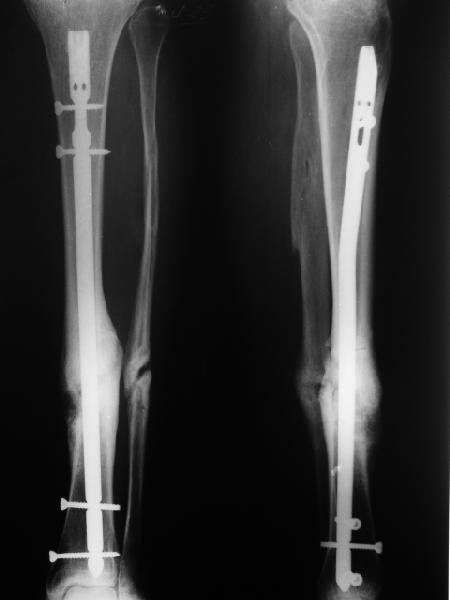

Это тугой ложный сустав, ничего там не надо резецировать, достаточно или его в аппарате дозированно растянуть и ось исправить, или чрескожную парафокальную остеотомию сделать - надо по второй ноге посмотреть, что там с длиной, тогда и выбрать.

Пример с закрытой дистракцией вот.